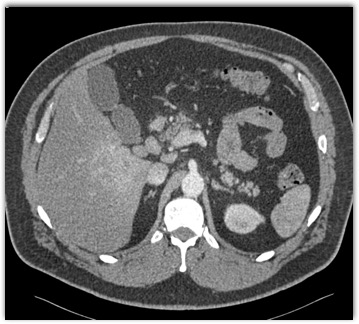

The best diagnosis in this case is?

NASH

focal liver sparing

hepatoma

cirrhosis